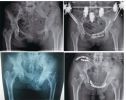

骨二科成功救治不稳定性骨盆骨折两例

骨盆由左右对称的髂骨、耻骨、坐骨和后方的骶骨组成。它承担了保护盆腔重要脏器(如膀胱、生殖器官)的任务,同时也是承接躯体上半部和下半部的“连接器”。骨盆因为解剖位置特殊,加上周围肌肉等组织丰富,一般很少发生骨折。不过,随着现代交通和建筑业的发...